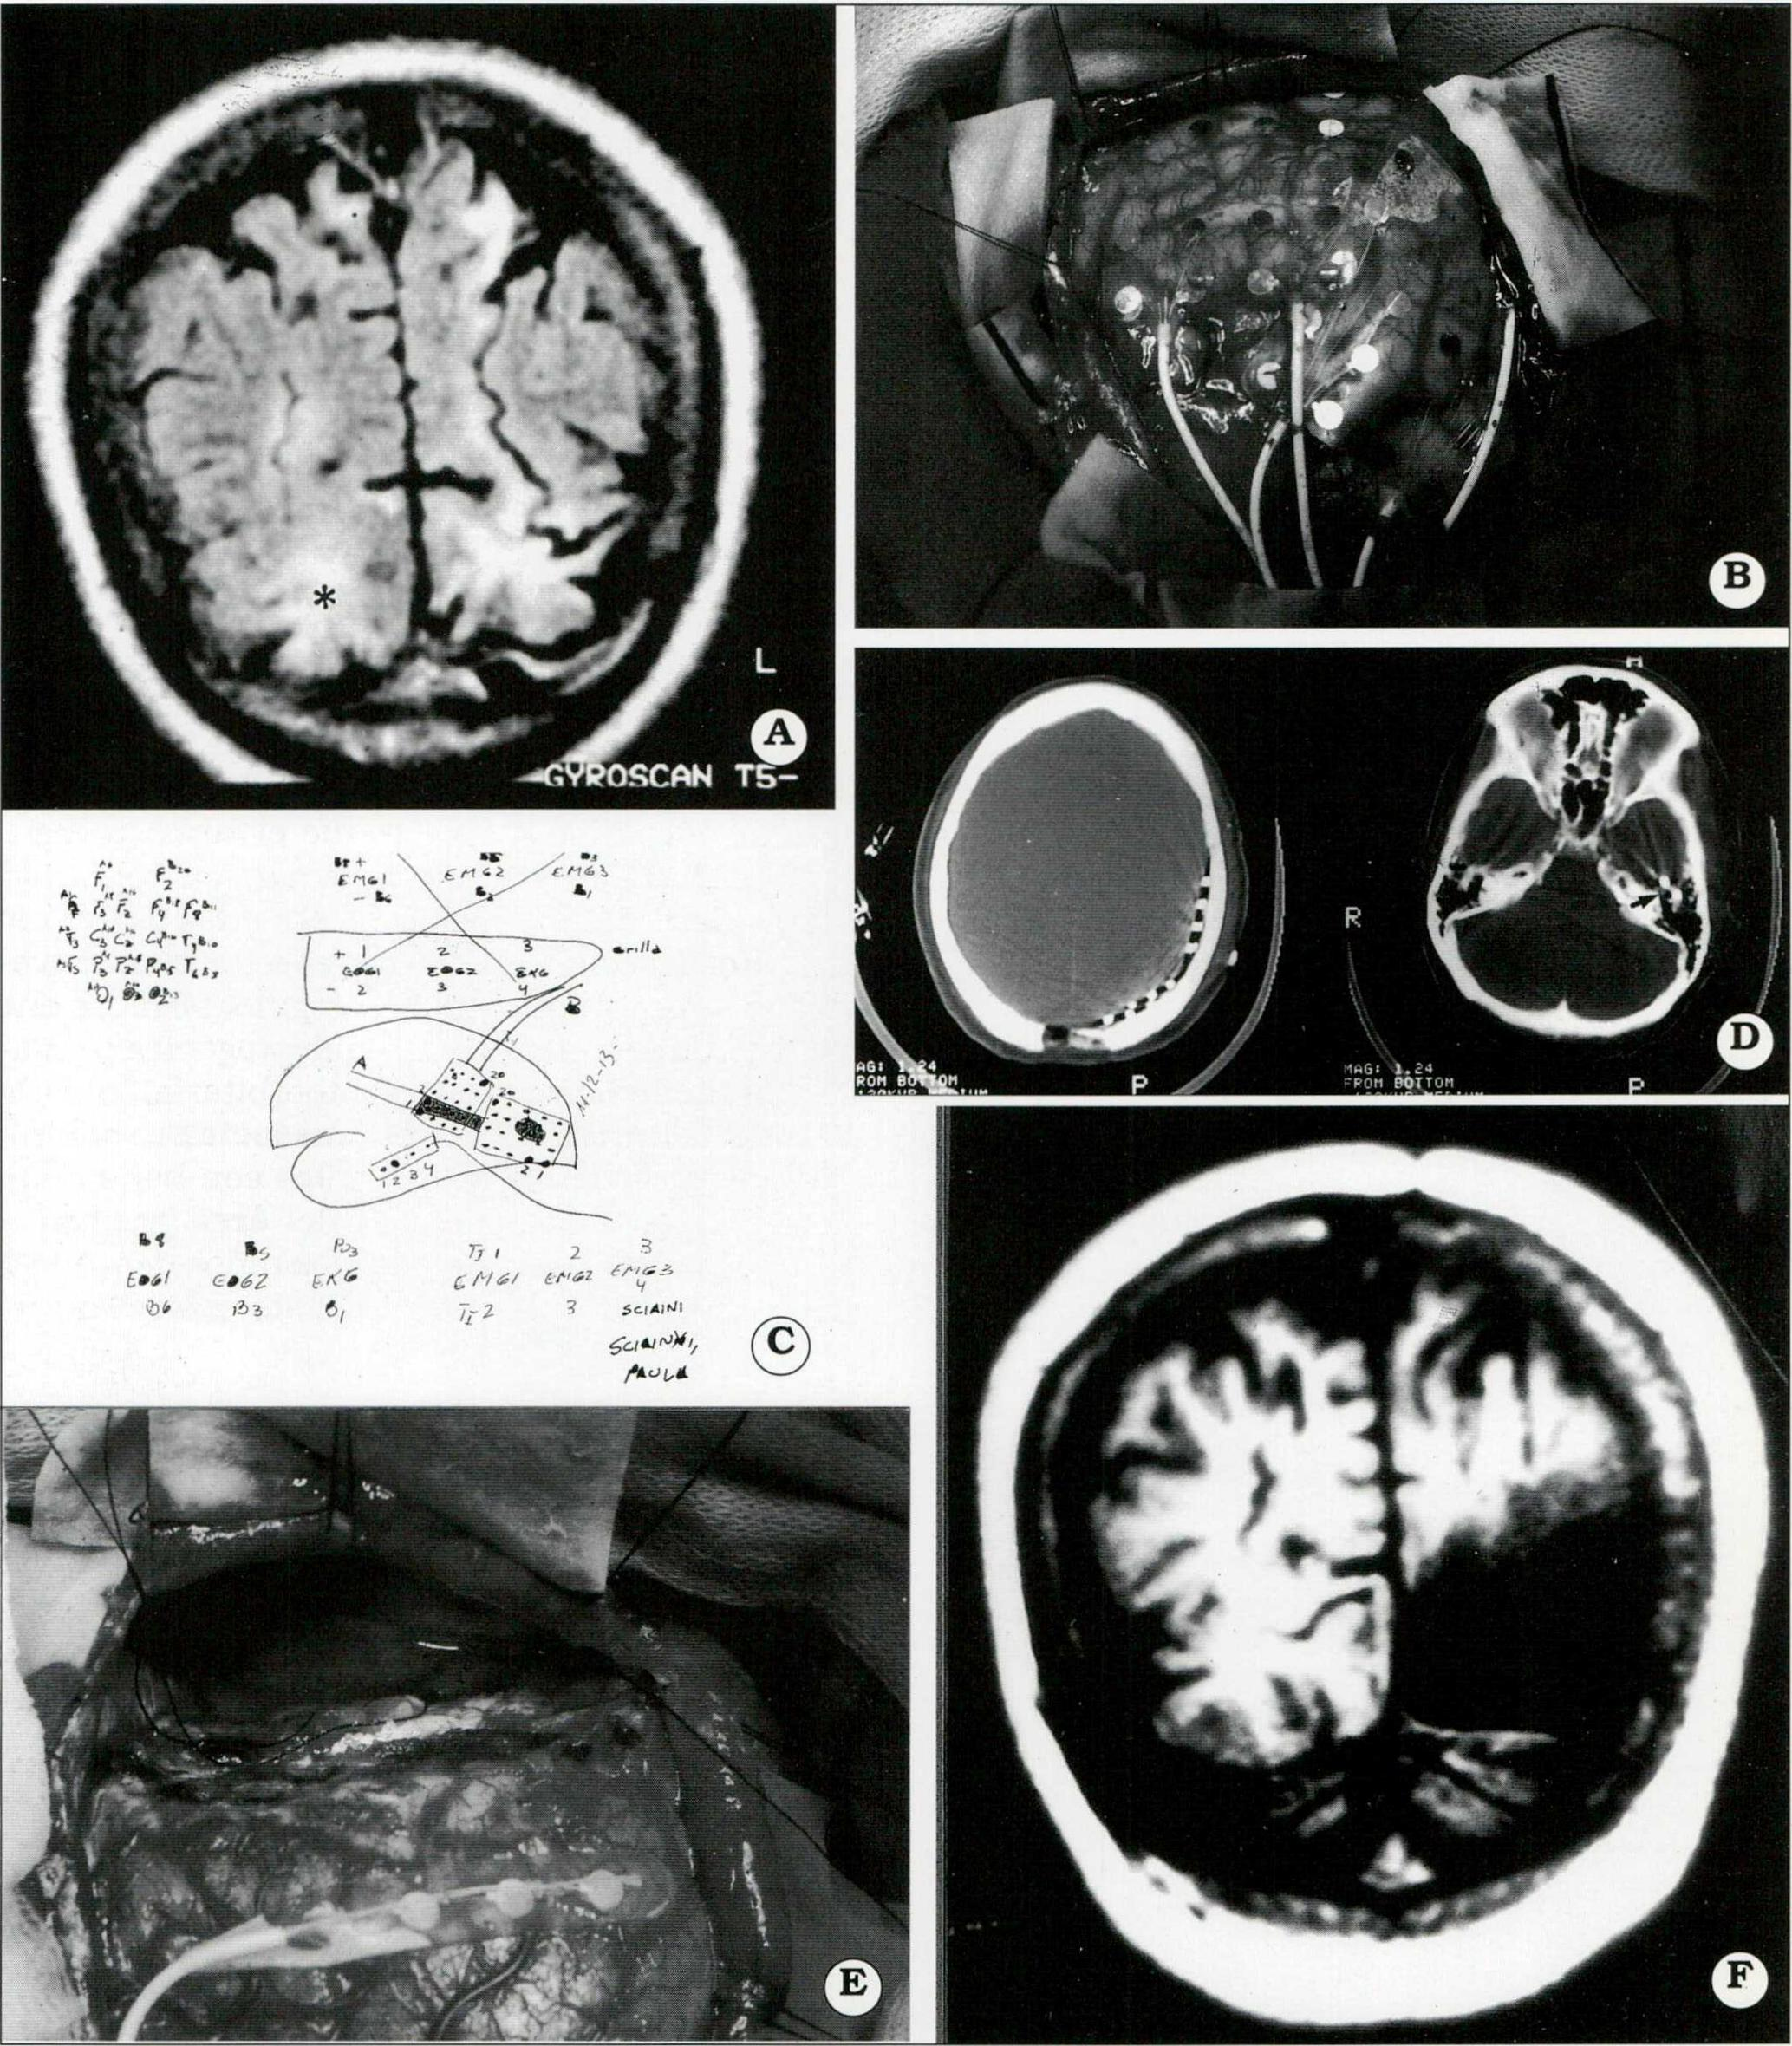

En 11/60 pacientes estudiados con videotelemetría fue necesario recurrir a la utilización de electrodos intracraneanos9. Esto implicó efectuar cirugías en dos tiempos: uno inicial para la colocación de los electrodos y el traslado del paciente a la unidad de Video-telemetría; luego de captar un número suficiente de crisis, no menos de 3 a 5, se realizó segundo tiempo quirúrgico acorde a la estrategia definida previamente. (Figs. 3 y 4).

Fig . 4. A. IRM preoperatoria que muestra una lesión occipital, hiperintensa en T I (estrella). B. Colocación de 2 plaquetas de 20 electrodos subdurales parietooccipitales. C. Esquema intraoperatorio, orientador para el trabajo del equipo de neurofisiología, durante la videotelemetría con los electrodos implantados. D. TAC con ventana ósea. Muestra la ubicación de los electrodos parieto-occipitales y en la base del lóbulo temporal (a la derecha, flecha). E. Polectomía occipital derecha. F. IRM postoperatoria.

En cuanto a los procedimientos quirúrgicos18, las lesionectomías (27/68) se utilizaron en aquellos casos en los que diferentes tipos de lesiones tenían algún grado de relación con la ZEP. Se hicieron bajo guía ECoG. Las estrategias de resección fueron: lesionectomías puras, con margen o ampliadas a áreas epileptogénicas alejadas de la lesión.

El sustento para la selección de cada procedimiento lo dio la ECoG, el tipo de lesión, su extensión y la relación con el área central y del lenguaje, zonas en las que obviamente las resecciones fueron más económicas (Fig 5).